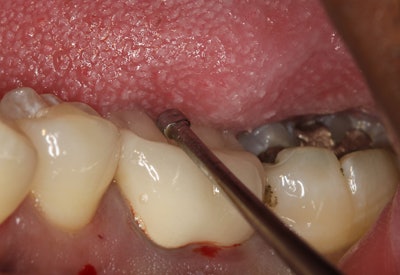

The crown is removed from the tooth. I have historically cut or split crowns with a bur in a high-speed handpiece. This technique can be time-consuming and can put wear on your handpiece while using several expensive burs.

A product I recently evaluated, the WAMkey (Golden Dental Solutions), has changed how I approach the removal of crowns and bridges (figure 4). The Wamkey Intro Kit contains three keys in oval-shaped heads: sizes small, medium, and large.

The technique is relatively simple.

- Create a small window in the crown that is approximately 1 mm to 2 mm in diameter where the preparation/crown occlusal interface is assumed to be located (figure 5). The opening should be made closer to the occlusal surface for metal crowns and generally about halfway between the occlusal surface and the margin for porcelain or PFM crowns.